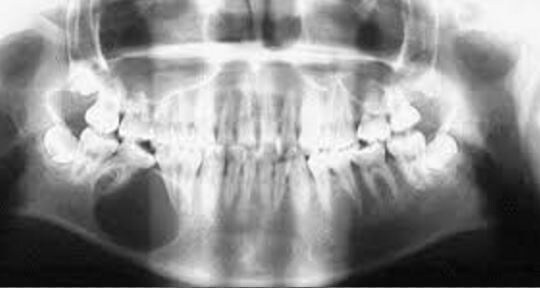

3. Рентгенологическое исследование

Это ключевой метод диагностики кист челюсти. Рентгенография позволяет увидеть очаг разрежения костной ткани, определить размеры и форму кисты, её локализацию относительно корней зубов и анатомических структур. Наиболее информативными являются панорамная рентгенограмма (ортопантомограмма), внутриротовая рентгенограмма и компьютерная томография (КТ).

· Панорамная рентгенограмма: даёт общее представление о состоянии обеих челюстей, помогает оценить расположение кисты относительно соседних зубов и анатомических образований.